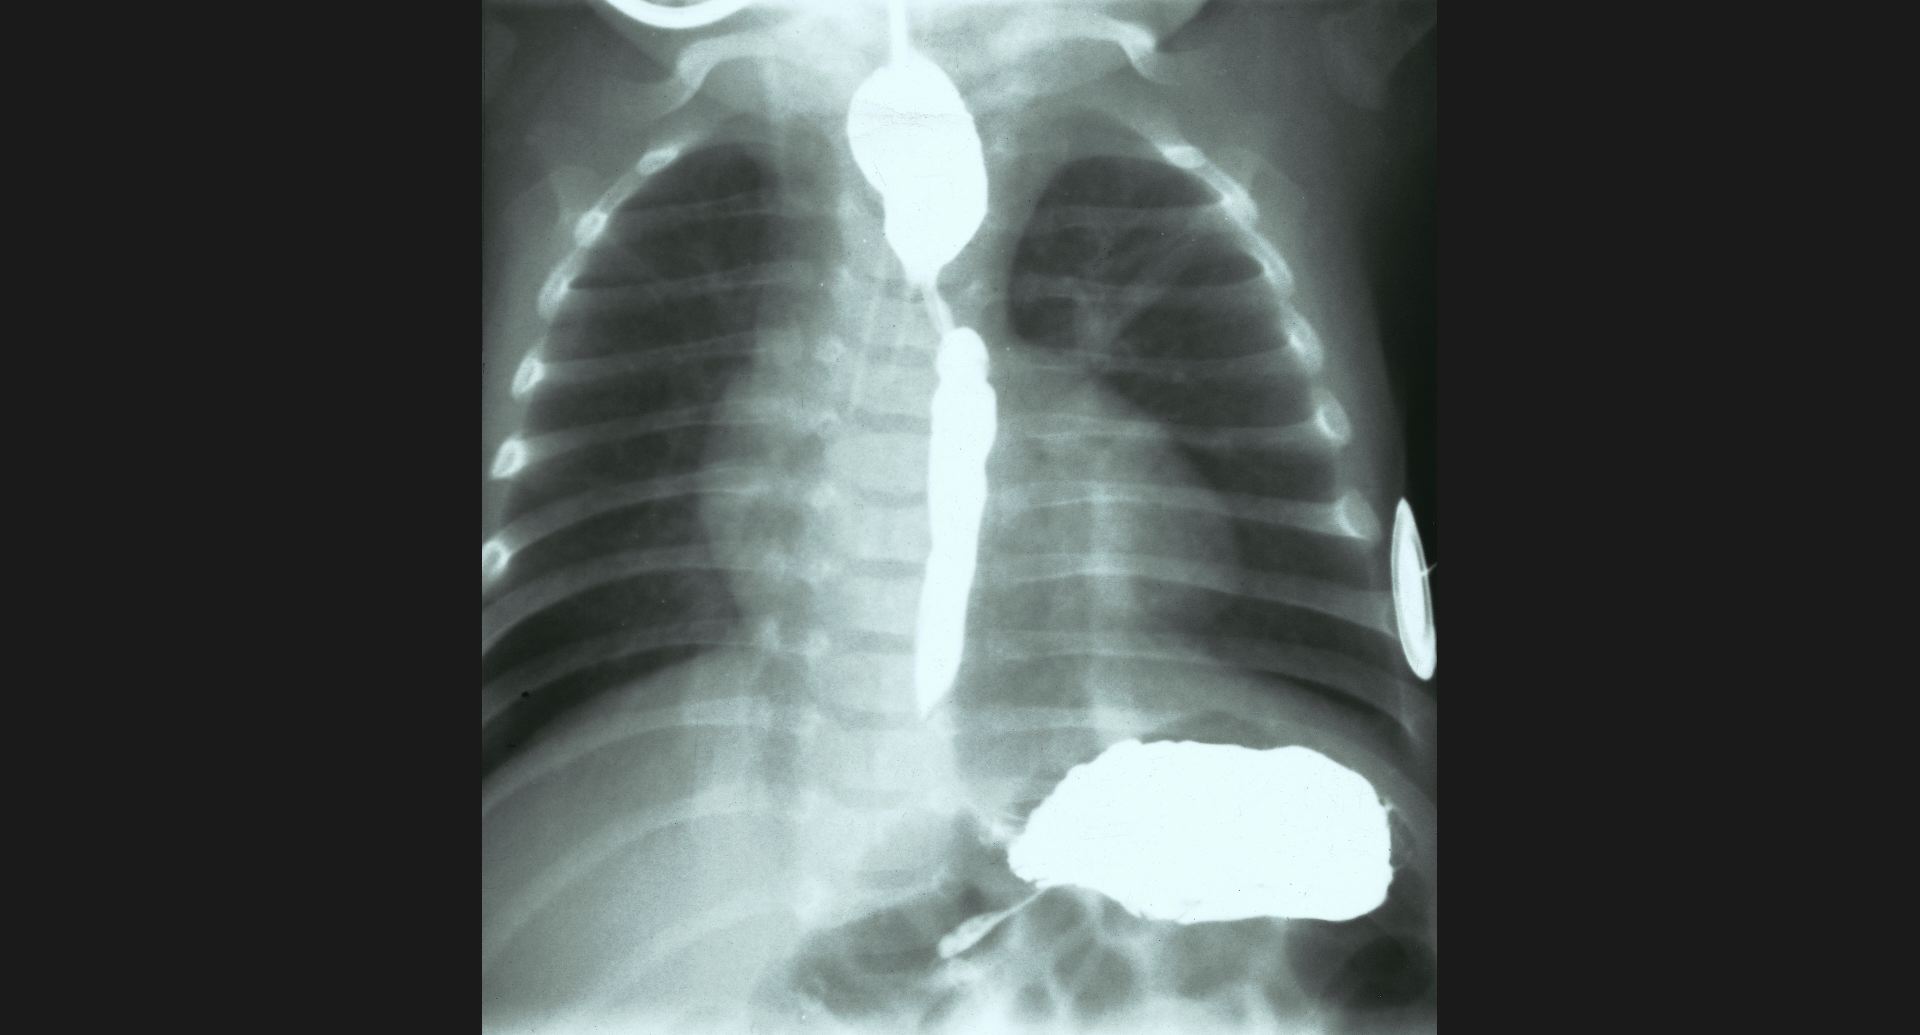

fig.3(105KB) :食道狭窄、肺炎

食道狭窄は、double aortic archによる。 肺炎は、造影の細かいところ。